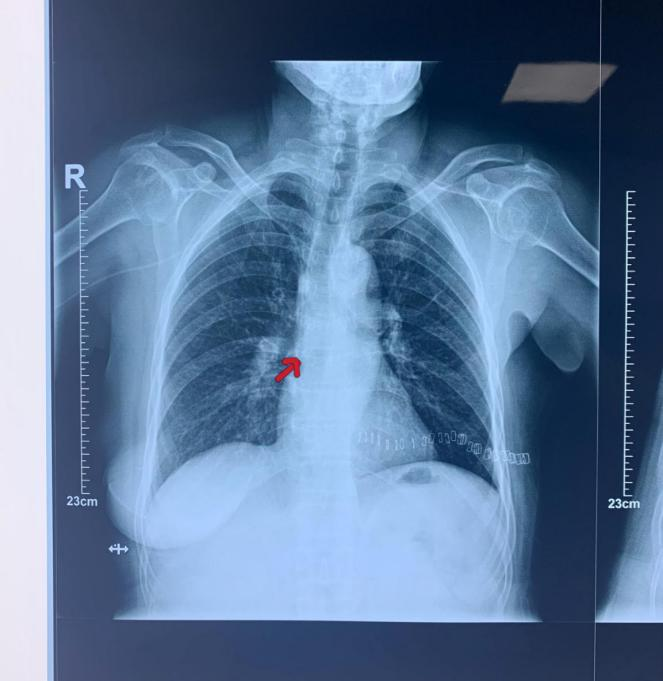

患者女性,诊断为乳腺癌,行乳腺癌改良根治术后,因病情需要进行化学治疗。为了减少化疗期间普通静脉穿刺容易造成的外周静脉炎症、血栓、血管硬化及闭塞的风险,经主管医生和静疗小组成员对患者病情以及血管条件综合评估后,建议留置手臂式输液装置。与患者及家属沟通后,在乳腺诊疗中心主任吴瑛琦、主治医生于光辉、孙振莹以及静脉治疗小组成员刘志娟共同协作下,成功为患者实施“手臂式静脉输液装置植入术”。手术选择经贵要静脉穿刺置入,在超声引导下,一次穿刺成功,手术时长20分钟,患者手术全程清醒,无不适症状,伤口对合良好,术中应用腔内心电图尖端定位技术,准确将导管尖端送入理想位置,术后经过影像学评估,导管位置良好准确,为患者下一步的治疗创造了必要条件。